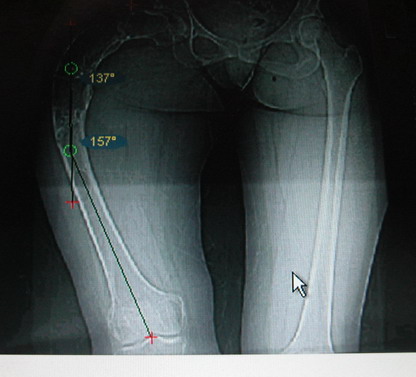

Моё мнение, что двойная остеотомия бедра с аппаратом Илизарова + Гексаподный механизм, или Тэйлора, В данной ситуации является методом выбора. Я очень извеняюсь за качество прилагаемых снимков, в которых я постарался отразить разницу междe одной и двумя остеотомиями бедра.

Собственно сустав не беспокоит, объем движений полный. По скиаграммам получается, что достаточно одной остеотомии на вершине деформации, чтобы восстановить длину и вывести коленный сустав в нужное положение.

Т.к. укорочение 7 см, то начинать будем с соеотомии и коррекции аппаратом. Спасибо

Возможна аппаратная коррекция оси с формированием клиновидного регенерата, которая решила бы и проблему укорочения (что, впрочем, нужно уточнить по схеме, сделанной по рентгенограмме с хорошим захватом смежных суставов - схемка по присланному снимку в приложении). По окончании коррекции - блокируемый стержень, который и сократит время пребывания в аппарате, и вообще возврата к нормальной жизни, а также будет мерой профилактики патологических переломов.